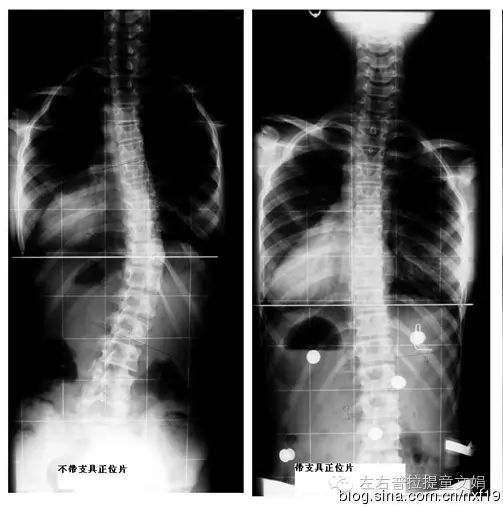

二、矫正支架的使用治疗:

适用于脊椎侧弯的角度介于20度到40度之间的情况;除了做上面提到的复健运动治疗外,还必须加上使用矫正性支架。